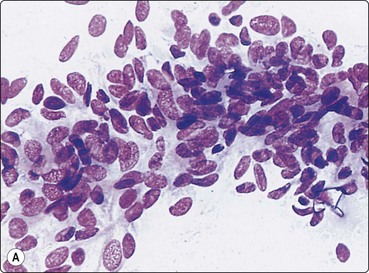

image image image

Fig. 10.23 Hepatocellular carcinoma, fibrolamellar type

(A) Neoplastic cells adherent to fragments of lamellar collagen (MGG, HP); (B) Very large, malignant hepatocytes with prominent nucleoli and abundant granular cytoplasm (MGG, HP oil); (C) Corresponding tissue section (H&E, IP).

image

Fig. 10.24 Hepatocellular carcinoma

Well-differentiated tumor composed of poorly cohesive hepatocytic cells with mild anisokaryosis but large nucleoli; differentiation from adenoma difficult (MGG, HP).

Fig. 10.27 Cholangiocarcinoma

(A) Disorganized clusters of irregular but not very pleomorphic tumor cells with pale cytoplasm and relatively small nuclei (MGG, HP); (B) Disorganized cluster of mildly pleomorphic epithelial cells with hyperchromatic nuclei and prominent nucleoli (MGG, HP); (C) Corresponding tissue section (H&E, IP).